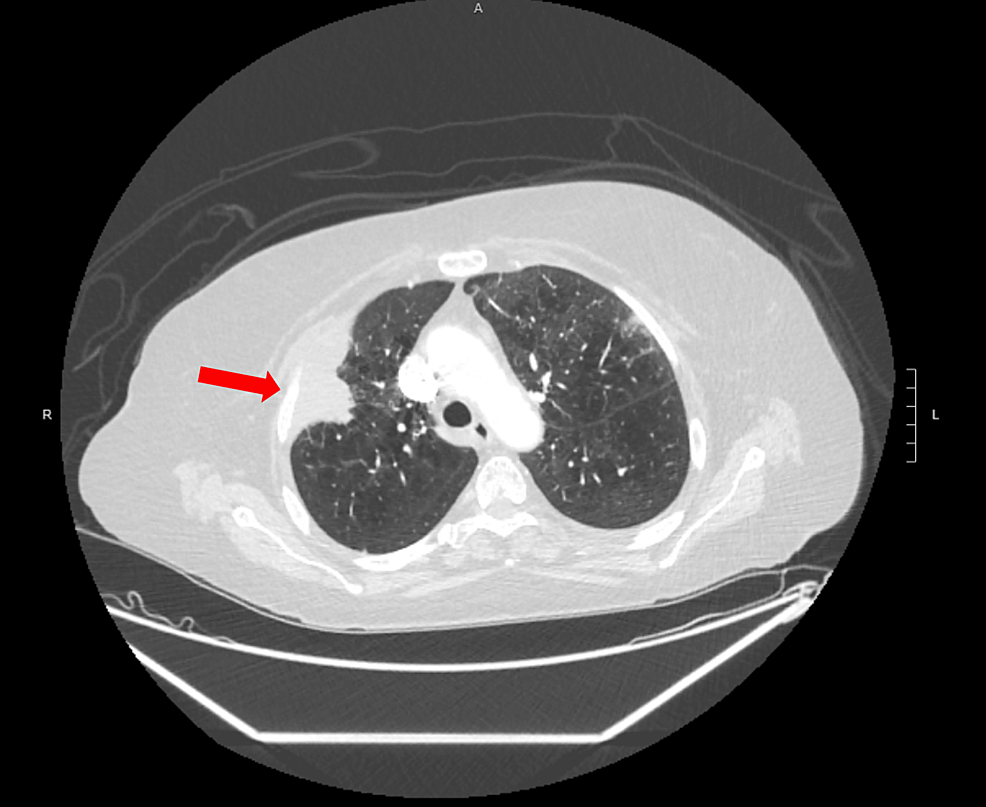

Pulmonary sarcomatous carcinoma is a rare subtype of non-small cell lung cancer (NSCLC). This cancer has very low survival rates primarily due to its aggressive nature and propensity for early s...